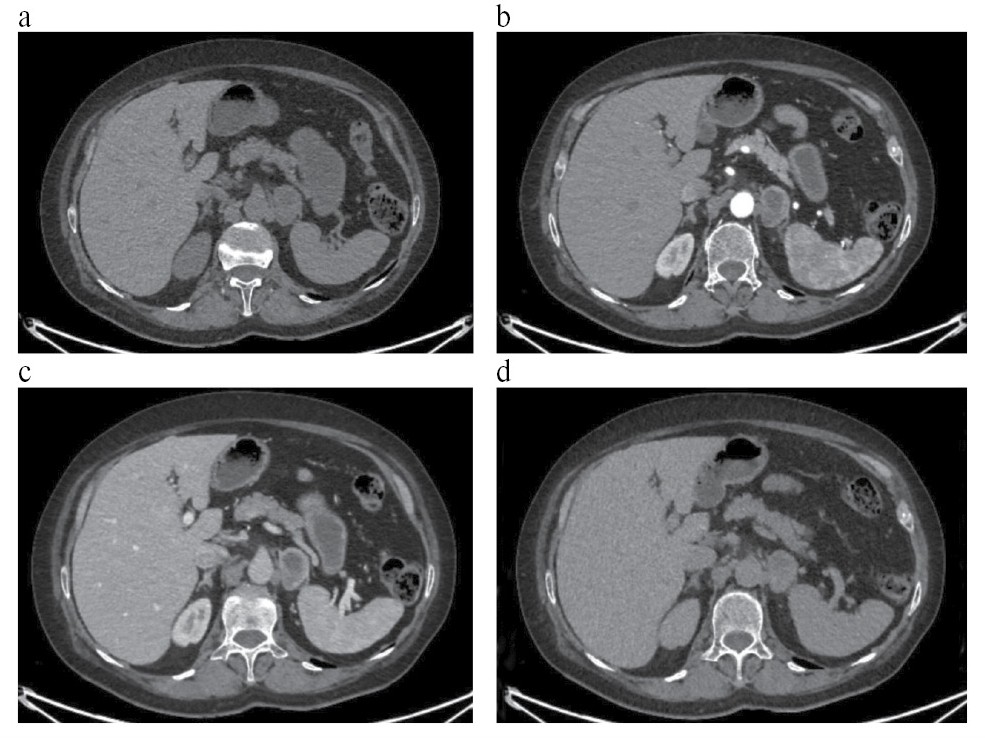

При визуальной оценке КТ-изображений ФХЦ отмечались различия по структуре и характеру контрастирования образований без связи с размерами (рис. 1–3).

Рис. 2. КТ с КУ: ФХЦ правого надпочечника размерами 41×33 мм, однородной структуры: a – NAT: плотность образования 42 ед.Н; b – ART: образование интенсивно неравномерно накапливает контрастный препарат до 227 ед.Н; c – VEN: плотность образования 113 ед.Н; d – DEL: образование «сбрасывает» контрастный препарат до 63 ед.Н.

Fig. 2. Contrast-enhanced CT: PCC of the right adrenal gland of 41×33 mm with homogeneous structure: a – NAT: density of the mass of 42 HU; b – ART: the mass intensively and unevenly uptakes the contrast agent up to 227 HU; c – VEN: density of the mass is up to 113 HU; d – DEL: the mass releases the contrast agent from the peripheral zones up to 63 HU.